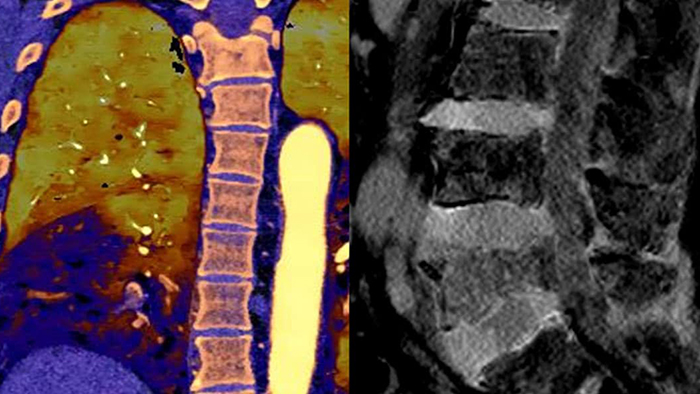

With detector-based spectral, you acquire multiple layers of data—conventional and spectral—within a single exposure and without special scan modes for improved tissue characterization and visualization.

Scan as usual A single scan for fast, low-dose conventional and spectral data for every patient, every time.

Always available 100% spectral, 100% of the time for results that are always available on-demand, even retrospectively.

Reduced follow-up exams Improved tissue characterization and visualization may reduce the need for follow-up scanning for sub-optimal exams and incidental findings.